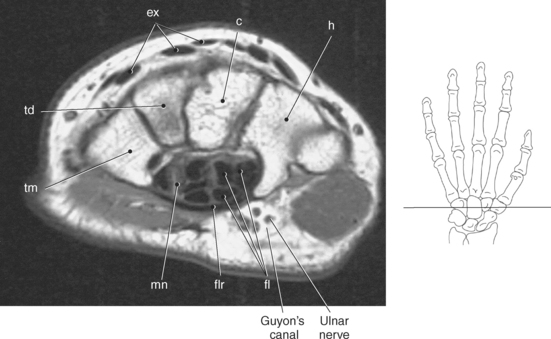

Numerous ligaments provide additional stability to the wrist. The extrinsic ligaments reinforce the joint cavity surrounding the carpal region and include palmar and dorsal radial carpal ligaments, the radial and ulnar collateral ligaments, and the TFCC (Figures 9.115 through 9.117). The many articulations between the carpal bones are supported by the intercarpal ligaments or intrinsic ligaments that connect the carpal bones to each other (Figure 9.115). The configuration of the intrinsic ligaments, metacarpal ligaments, and triangular fibrocartilage complex creates five different joint compartments that can be demonstrated at arthrography: (1) compartment of the first carpometacarpal articulation, (2) common carpometacarpal compartment, (3) mediocarpal compartment, (4) intermetacarpal compartment, and (5) radiocarpal compartment (Figure 9.115). The carpal tunnel is created by the concave arrangement of the carpal bones (Figure 9.103). A thick ligamentous band called the flexor retinaculum (transverse carpal ligament) stretches across the carpal tunnel to create an enclosure for the passage of tendons and the median nerve (Figures 9.118 through 9.120). The flexor retinaculum inserts medially on the pisiform and hook of the hamate and spans the wrist to insert laterally on the scaphoid and trapezium. In addition to the carpal tunnel, another tunnel called Guyon’s canal is formed where the ulnar extension of the flexor retinaculum continues over the pisiform and hamate. This creates a potential site for compression of the ulnar nerve (Figures 9.118, top, and 9.119). The extensor retinaculum (dorsal carpal ligament), located dorsally, is much thinner. It attaches medially to the ulnar styloid process, triquetrum, and pisiform and laterally to the lateral margin of the radius (Figure 9.120, left). Along its course it forms six fibroosseous tunnels for the passage of the synovial sheaths containing the extensor tendons (Figure 9.118, bottom).

Figure 9.118 Axial view of carpal tunnel and flexor tendons. Top, Extensor tendons. Bottom, Compartments.

Figure 9.119 Axial, T1-weighted MR scan of wrist with flexor and extensor tendons.

Key: ex, Extensor tendons; c, capitate; h, hamate; fl, flexor tendons; flr, flexor retinaculum; mn, median nerve; tm, trapezium; td, trapezoid.